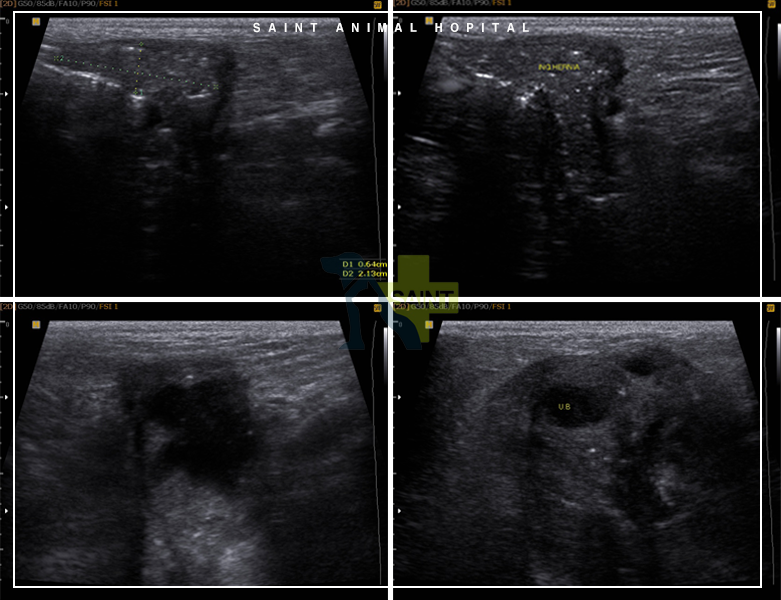

초음파와 방사선 검사에서 탈장이 확인됐지만 특정 조직에 대한 판단은 어려웠습니다.직장 회음부 탈장이 가장 의심스러웠어요.꿈*이 나이가 많아서 학부모님과 충분한 상담 후 수술을 진행하기로 결정하였습니다.

피부를 절개해 탈장한 부위를 노출시키자 탈장한 조직은 예상치 못한 방광이었습니다.초음파로 방광경부가 제대로 확인되지 않은 탈장으로 인한 문제라는 것도 알았습니다.